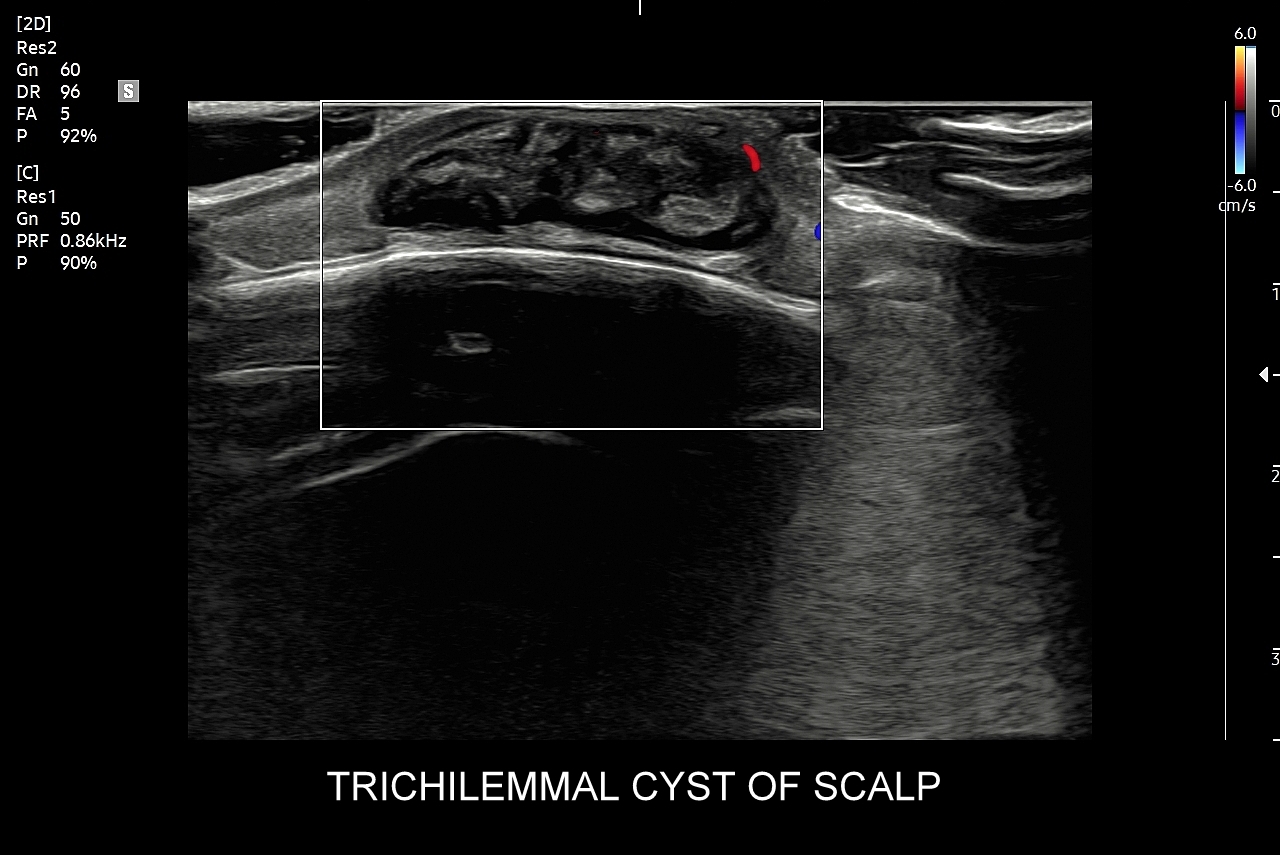

Badanie USG skóry i powłok jest metodą diagnostyczną, która swoją czułością oraz dokładnością przewyższa w ocenie patologii powłok badanie rezonansem magnetycznym. W obrębie powłok ciała w badaniu USG najczęściej rozpoznaje się różnorodne guzy oraz stany zapalne. Wśród guzów dominują łagodne tłuszczaki, kaszaki i torbiele inkluzyjne, a także przepukliny. U młodszych pacjentów często wykrywa się naczyniaki. Rzadziej spotkane są guzy złośliwe jak mięsaki, czy przerzuty nowotworowe. W pracowni USG dr Szczepańskiego poza wizualną oceną guzów powłok przeprowadzana jest ich ocena biologii w kontekście cech złośliwości i oceny przewidywalnego tempa wzrostu.

Niektóre patologie miękkotkankowe mają predylekcję do występowania w określonych obszarach ciała. Przykładowo w obrębie szyi spotyka się torbiele boczne, torbiele centralne szyi oraz inne pozostałości po embrionalnych łukach skrzelowych. Na karku, szyi oraz w pachwinach badanie USG wykorzystywane jest często przy ocenie i różnicowaniu węzłów chłonnych, które mogą ulegać powiększeniu w przebiegu chorób nowotworowych, rozrostowych, jak i infekcyjnych (np. przeziębienie, choroba kociego pazura). Z kolei na plecach i skórze głowy dość często lokalizują się kaszaki, a na dłoniach i stopach włókniaki rozścięgien.